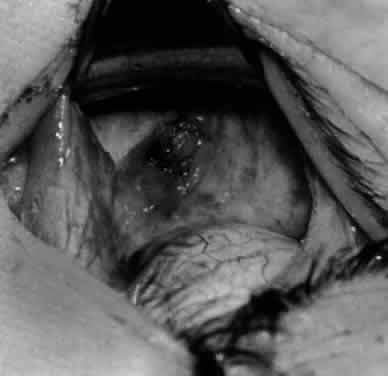

Fig. 17. Knots are tied to show the placement. The inferior oblique muscle is held on a Stevens muscle hook.

Fig. 18. The final position, with the inferior oblique muscle recessed 10 mm. The inferior rectus muscle is retracted with a Green muscle hook. As described in the text, the 14-mm recession would place the inferior oblique muscle over the inferior temporal vortex vein, and the 6-mm recession would place the inferior oblique muscle anterior and nasal to this position.